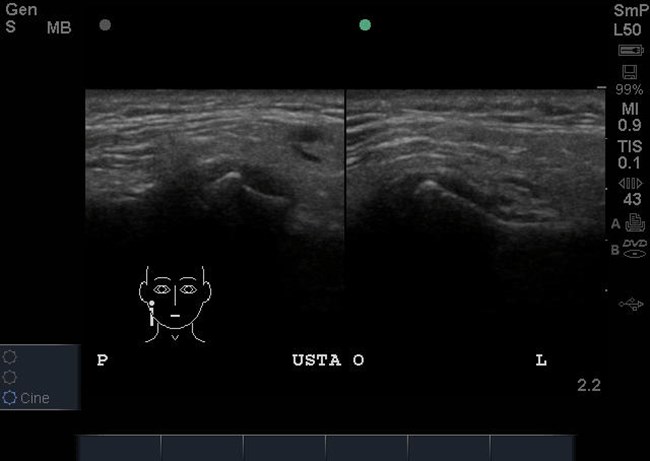

Następnie wykonano badanie ultrasonograficzne (USG) w celu oceny funkcji krążka stawowego ssż oraz mięśni narządu żucia. W prawym stawie skroniowo-żuchwowym stwierdzono doprzednie przemieszczenie krążka stawowego w zwarciu, które utrzymywało się w rozwarciu (ryc. 3 i 4). W lewym stawie skroniowo-żuchwowym krążek stawowy był położony na szczycie głowy żuchwy w zwarciu i rozwarciu (ryc. 3 i 4). Nie stwierdzono przerostu mięśni żwaczy ani patologii w obrębie mięśni mostkowo-obojczykowo-sutkowych, jak też powiększonych regionalnych węzłów chłonnych.

Ryc. 3. Przekroje strzałkowe ssż w zwarciu w badaniu USG. Widoczne doprzednie przemieszczenie krążka stawowego w prawym ssż. W lewym ssż krążek stawowy jest położony na szczycie głowy żuchwy.

Ryc. 4. Przekroje strzałkowe ssż w rozwarciu w badaniu USG. Utrzymuje się doprzednie przemieszczenie krążka w prawym ssż. W lewym ssż krążek znajduje się na szczycie guzka.